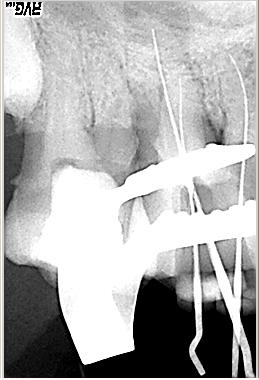

Röntgenmeßaufnahme

Röntgenmeßaufnahme nach vorgängig durchgeführter endometrischer Längenbestimmung